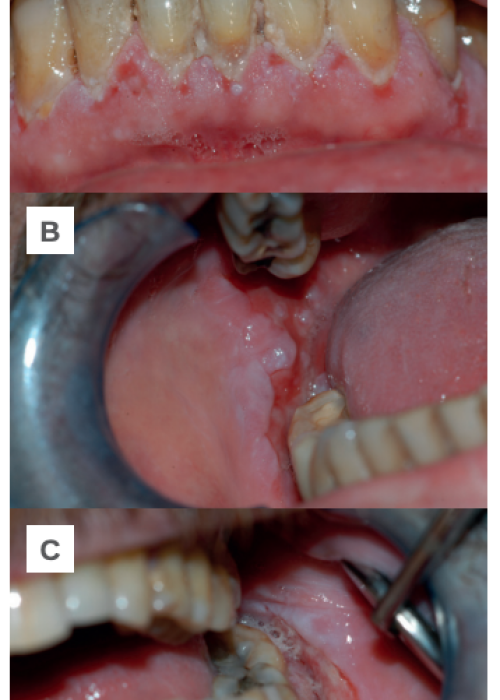

Clinical, radiographic and histomorphometric behaviour of the autologous tooth as a biomaterial in lateral access maxillary sinus elevation. Case report with six months of post-prosthetic loading follow-up

Comportamiento clínico, radiográfico e histomorfométrico del diente autólogo como biomaterial en elevación de seno maxilar de acceso lateral. Caso clínico con seis meses de seguimiento post-carga protésica